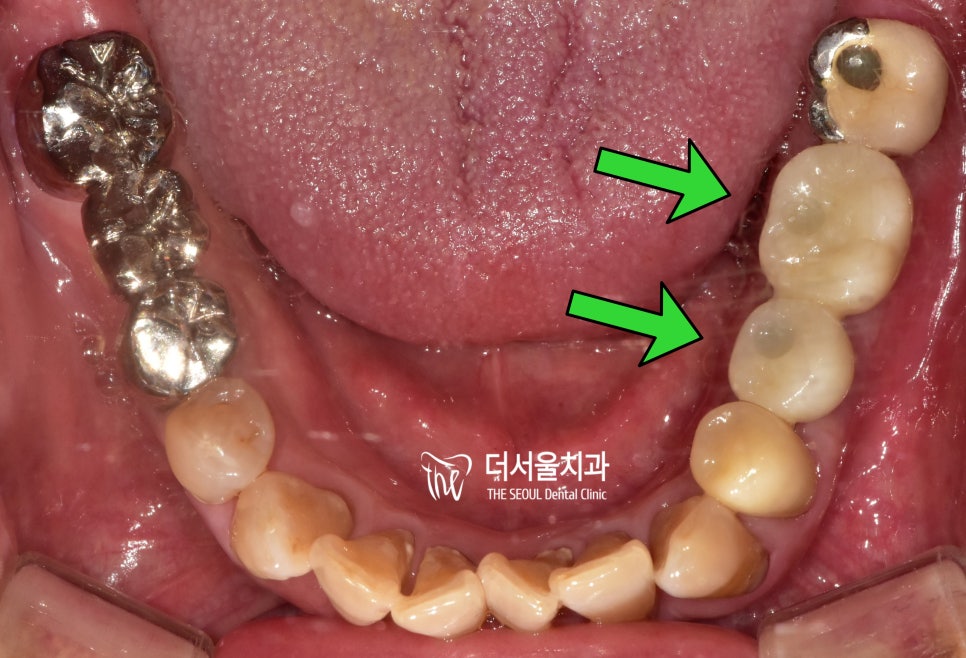

【 최종 세팅 및 수술 완료 】

맞춤형 어버트먼트와 크라운 제작까지

모두 완료되어 최종 세팅을 해드렸습니다.

윗니와 아랫니, 그리고 전체적 교합에

문제가 없는지 한 번 더 체크해줍니다.

또, 착용하고 나서

불편함이 느껴지는 부분은 없는지

여쭤보았으나,

크게 불편한 곳은 없으셔서

살짝 조정만 해드리며 끝났습니다.

모든 세팅이 완료되며

최종적으로 적용된 구내 모습입니다.

깔끔하게 잘 되었죠?